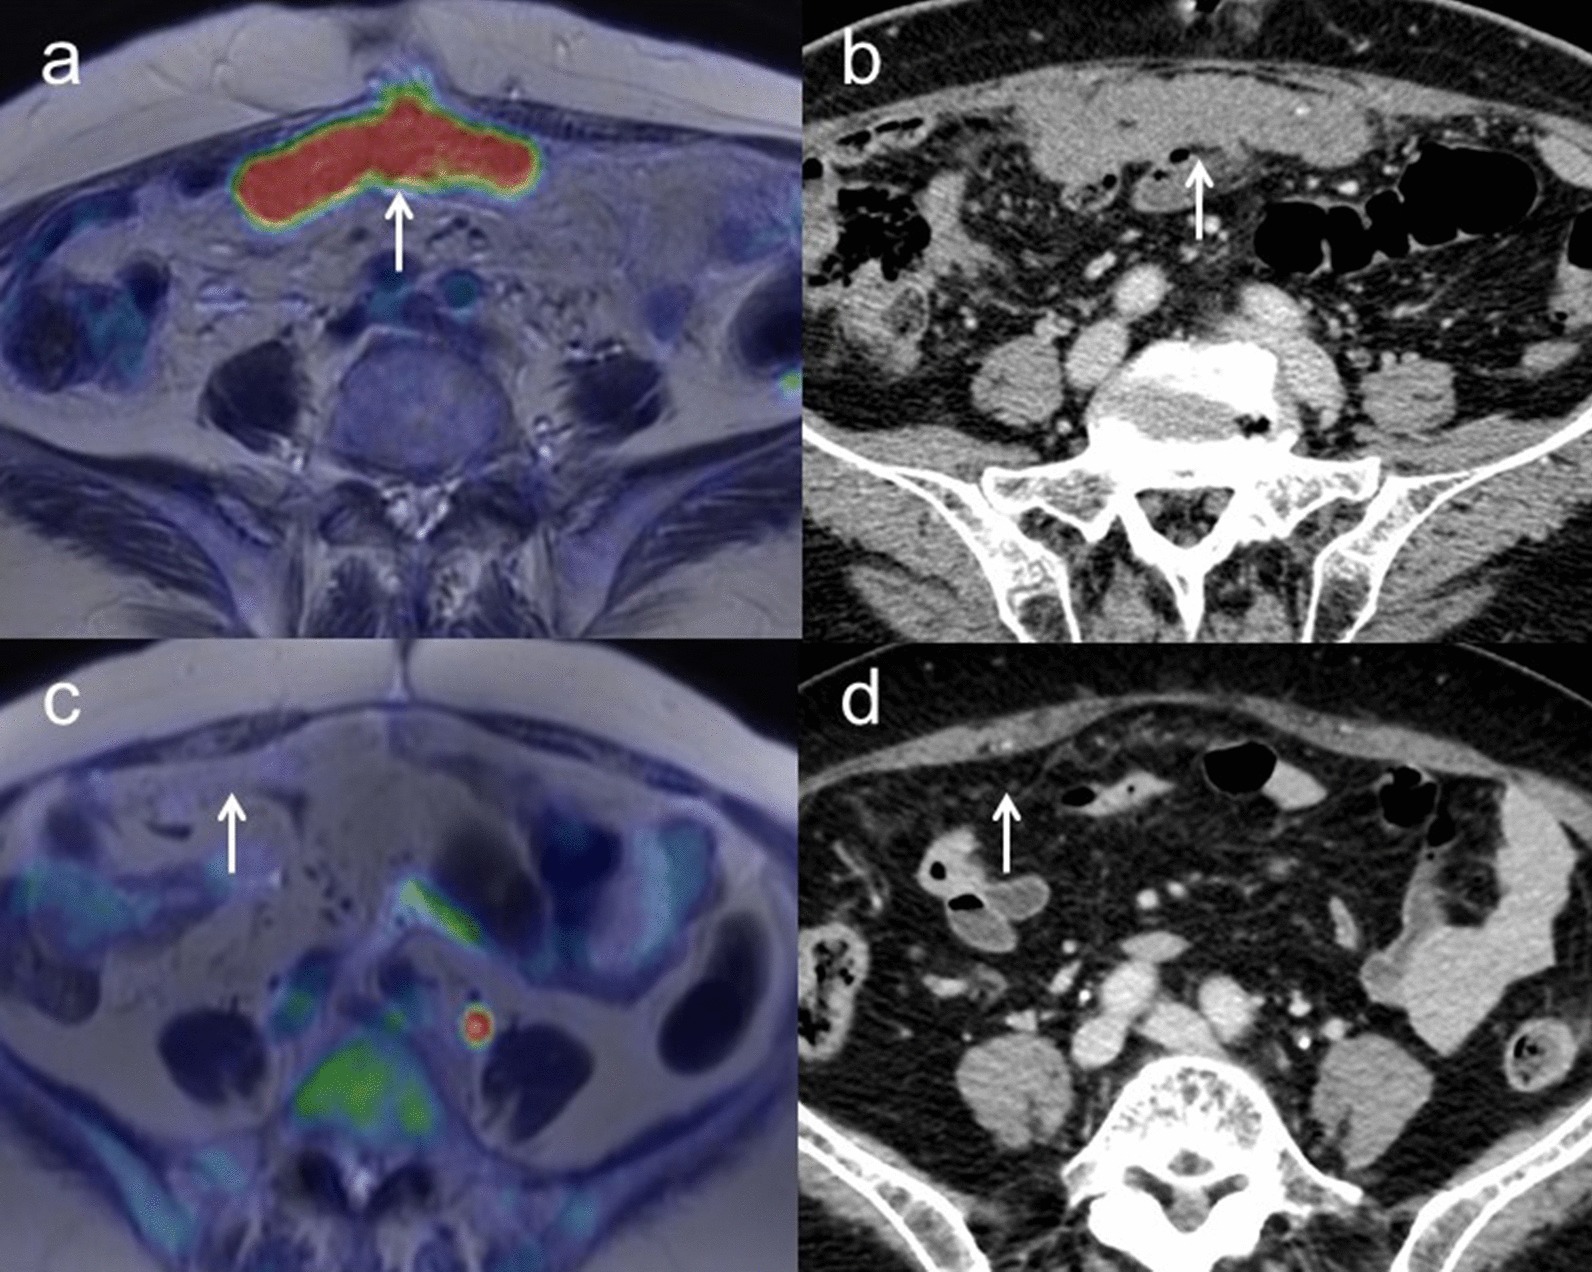

Residual disease for IDS after NAC

Sensitivity, specificity and accuracy for detecting residual disease for IDS after NAC were 71.4% (95% CI 0.71–0.71), 0% (95% CI 0.00–0.00) and 71.4% (95% CI 0.71–0.71) for [18F]FDG PET/MRI, and 57.1% (95% CI 0.57–0.57), 0% (95% CI 0.00–0.00) and 57.1% (95% CI 0.57–0.57) for ceCT, respectively (p = 1.00) (Table 5). Figure 5 shows representative images for detecting residual disease for IDS after NAC.

Fig. 5.

a A 71-year-old woman with ovarian cancer showing carcinomatous peritonitis and pleural effusion confirming the presence of malignant cells. After NAC, axial T2-weighted PET/MR image shows the omental cake with FDG uptake (arrow). b Contrast-enhanced CT shows the thickened omentum with slight enhancement (arrow). These findings strongly suggested potential residual disease, which was confirmed by histopathologic examination. c A 77-year-old woman with ovarian cancer with carcinomatous peritonitis and ascites confirming the presence of malignant cells. After NAC, axial T2-weighted PET/MR image shows the almost disappear of the omental cake and FDG uptake (arrow). d Contrast-enhanced CT also shows the almost disappear of thickness and enhancement of the omentum (arrow). These findings show the marked response to NAC. However, histopathologic examination confirmed residual disease comprising high-grade serous carcinoma with carcinomatous peritonitis

Sensitivity, specificity and accuracy for detecting recurrence were 100% (95% CI 0.88–1.00), 100% (95% CI 0.44–1.00) and 100% (95% CI 0.80–1.00) for [18F]FDG PET/MRI, and 88.9% (95% CI 0.76–0.89), 100% (95% CI 0.40–1.00) and 90.9% (95% CI 0.69–0.91) for ceCT, respectively (p = 1.00) (Table 5). Figure 6 shows representative images for recurrence.

Fig. 6.

a A 63-year-old woman with pathologically confirmed ovarian cancer. During follow-up after the successful initial treatment, including surgery and first-line chemotherapy, CA-125 gradually increased. Axial T2-weighted PET/MR image shows the left para-aortic lymph node with FDG uptake (arrow). b Contrast-enhanced CT shows the left para-aortic lymph node less than 1 cm in short-axis diameter with slightly enhancement (arrow). After second-line chemotherapy, this lymph node decreased in size and SUV, suggesting this node as a sign of recurrence